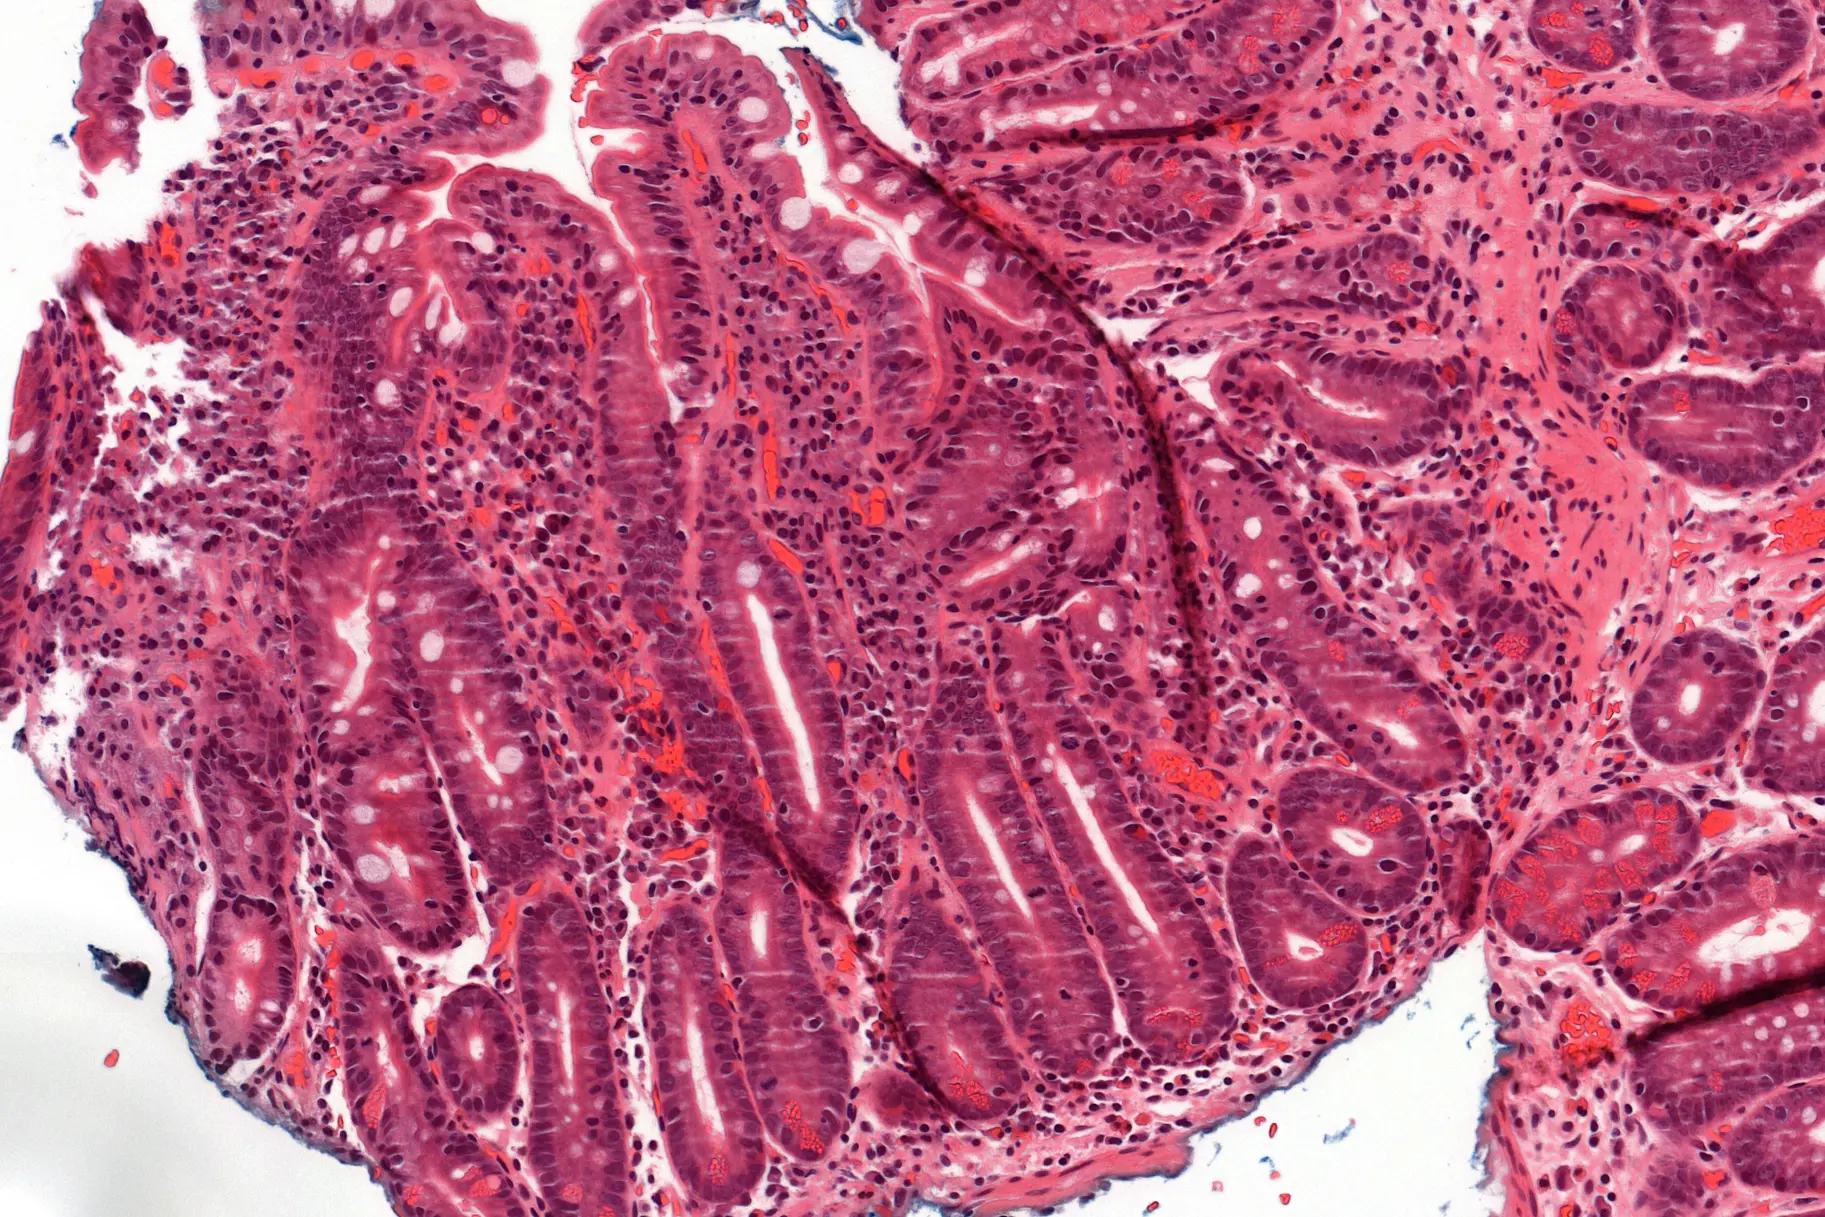

Foto: Oslo universitetssykehus, Mette H. Akerø

Når en cøliaker spiser gluten, fører en immunrespons mot gluten til betennelse i tynntarmen som gjør at tarmoverflaten endres. Tarmtottene, som er viktige for opptak av næring, blir kortere og erstattet av dype krypter. Den eneste behandlingen per i dag er å fjerne gluten fra kostholdet slik at betennelsen holdes i sjakk og tarmtottene regenereres.